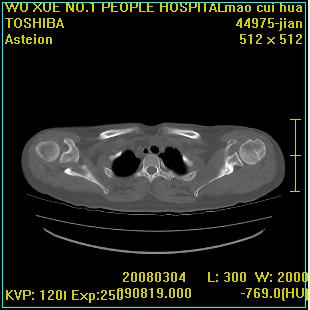

标题: CT12025:男,50岁,左肩活动受限半年。

肩关节骨质破坏呈小囊状,其周软组织轻度肿胀,余未见异常。

考虑:肩袖损伤。建议mri。

左侧肱骨头密度不均匀,高低混杂,周围软组织略肿胀,考虑结核性病变。

左侧肱骨头密度不均匀,高低混杂,髓腔密度稍高,周围软组织略肿胀,肌间隙模糊,考虑慢性骨髓炎可能。密切结合临床!